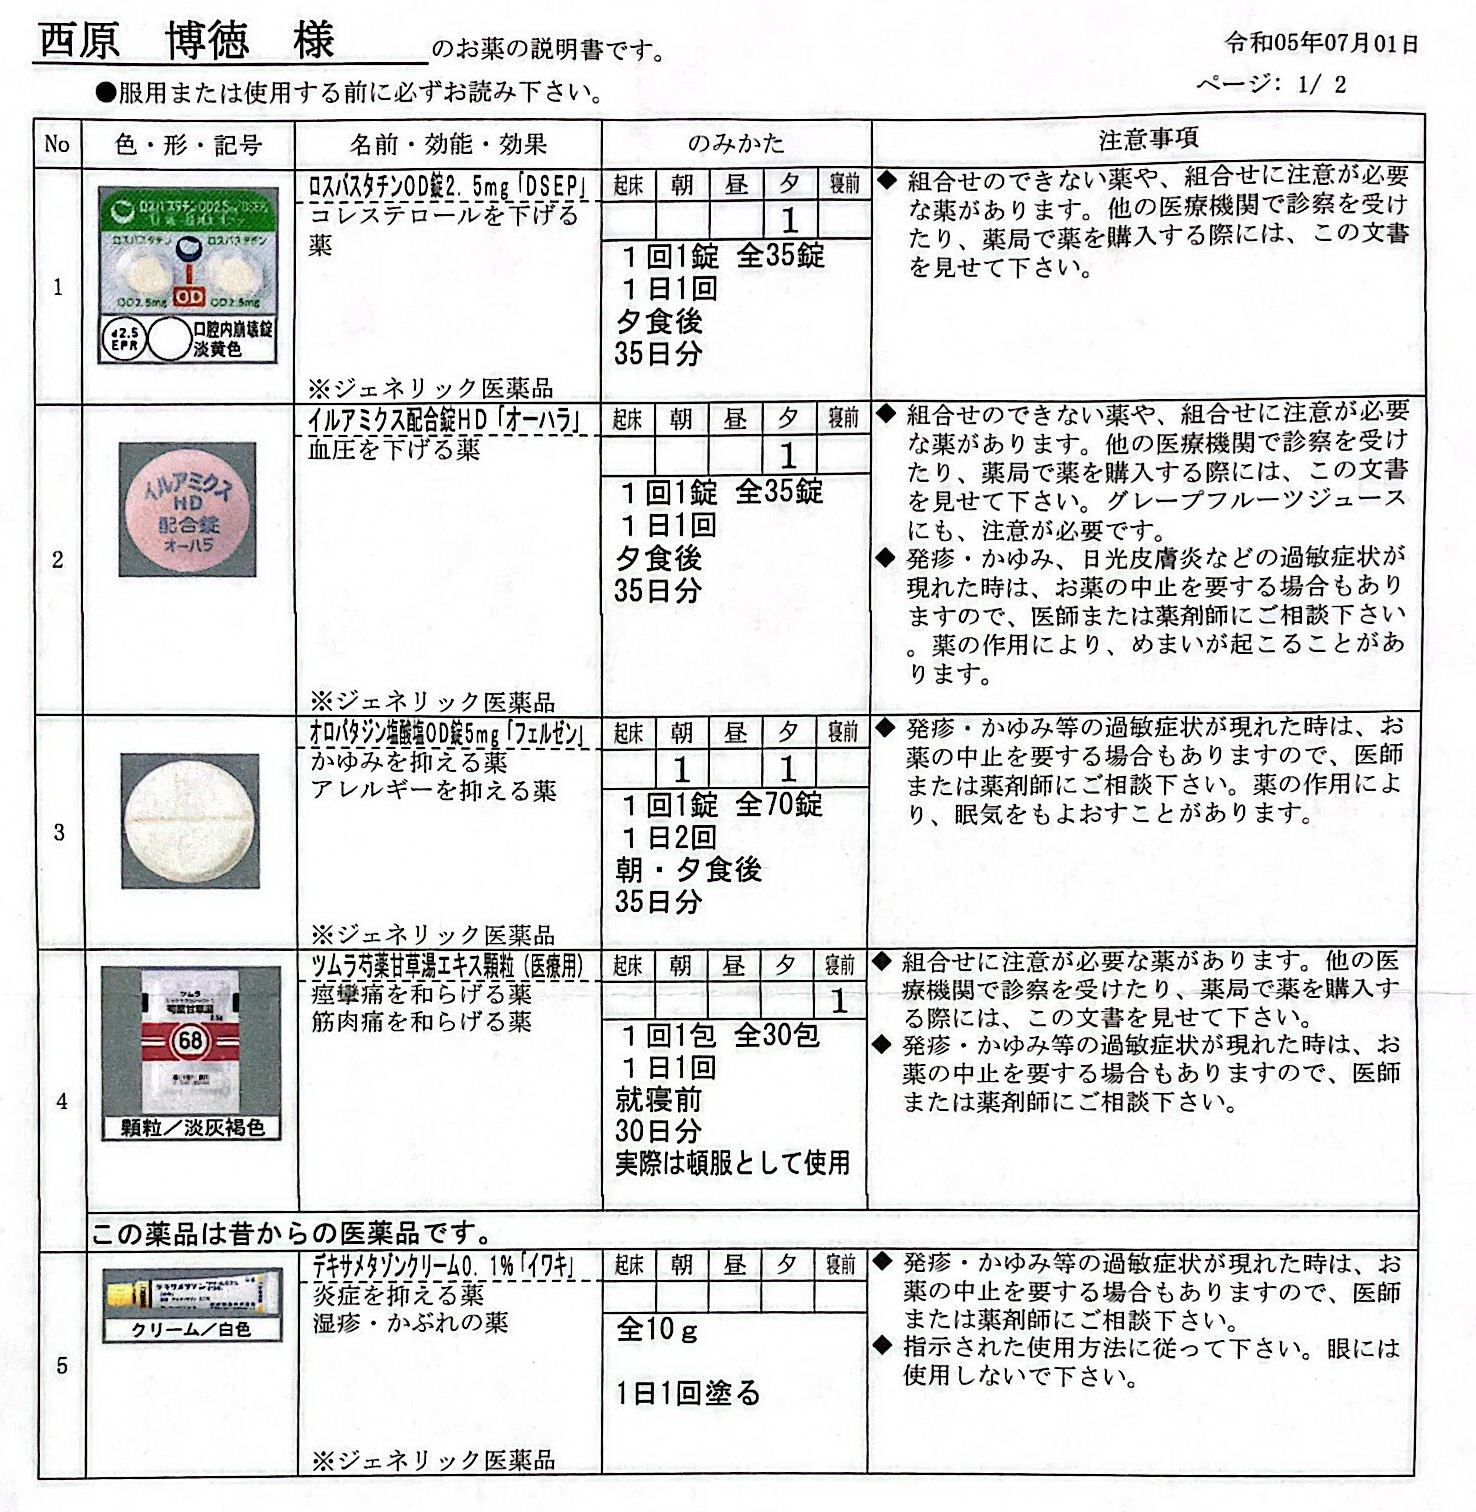

2021.11.13より 西原クリニック 0968-62-0622

2024.4.13 オロパタジンに戻る

2024.3.9 鼻炎と目のかゆみがひどく、オロパタジン⇒デザレックス&点眼薬 アレジオン に変更 2.10 血液検査結果

62:防風通聖散=膨満感対応 68:芍薬甘草湯=こむら返り対策